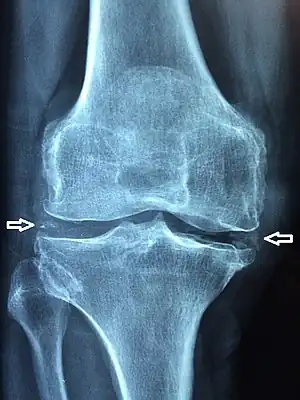

Chondrocalcinosis or cartilage calcification is calcification (accumulation of calcium salts) in hyaline cartilage and fibrocartilage.[1] It can be seen on radiography.

Chondrocalcinosis can be visualized on projectional radiography, CT scan, MRI, US, and nuclear medicine.[1] CT scans and MRIs show calcific masses (usually within the ligamentum flavum or joint capsule), however radiography is more successful.[1] At ultrasound, chondrocalcinosis may be depicted as echogenic foci with no acoustic shadow within the hyaline cartilage.[8] As with most conditions, chondrocalcinosis can present with similarity to other diseases such as ankylosing spondylitis and gout.[1]